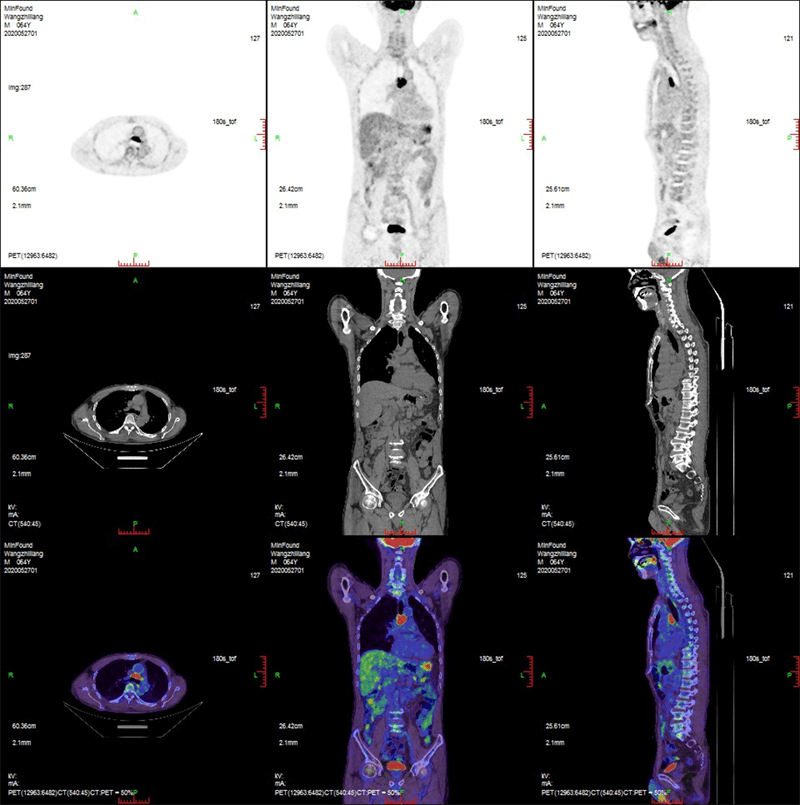

Clinical Gallery